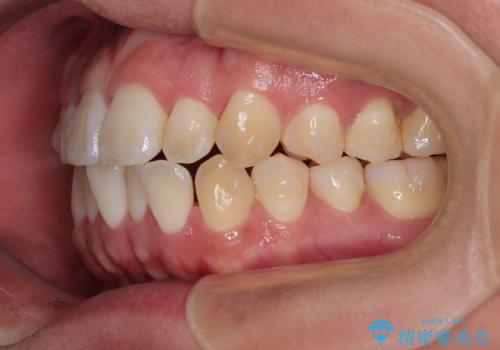

- 前歯の反対咬合などを気にして来院された患者様です。

ワイヤー矯正、マウスピース矯正どちらでも対応可能であったので、ご本人の希望によりインビザラインにて矯正治療を行うこととしました。

毎日の装着時間をしっかりと守ってくださり、1年強の短期間で、あっという間に治療を終えることができました。